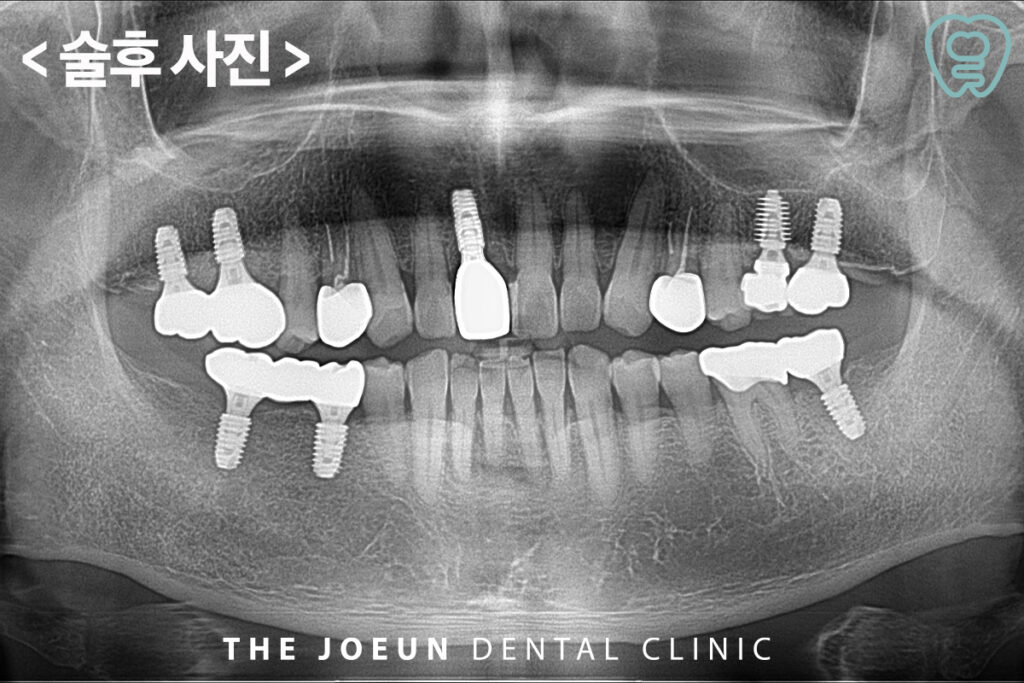

식립 3개월 후 최종 보철물까지 완성한 모습입니다.

다수의 임플란트에서는 보철물의 설계 또한 중요한 요소인데요. 여러개의 임플란트가 하나의 구조로 연결되는 경우도 있어 저작 시 발생하는 힘이 특정 부위에 집중되지 않도록 설계를 해야 합니다. 교합이 불안정할 경우 주위 뼈에 과도한 하중이 가해질 수 있으며 이는 장기적인 유지에 영향을 줄 수 있습니다. 따라서 치료 과정 전반에서 교합 조정과 보철 디자인이 반복적으로 검토됩니다.

다수의 임플란트는 기능뿐만 아니라 삶의 질 측면에서도 다양한 긍정적 변화를 가져올 수 있는데요. 우선 다양한 음식을 제한 없이 섭취할 수 있어 영양 섭취가 보다 원활해지고 음식물을 충분히 씹을 수 있어 소화 기능에도 도움이 됩니다. 다만 개별적인 임플란트보다 고려해야 할 변수가 많아 정밀하고 체계적인 진단 과정이 필수적으로 3D CT를 통해 턱뼈의 두께, 신경 위치, 골밀도 등을 면밀하게 파악해야 하며 이를 기반으로 환자분의 상태에 적합한 식립 방식과 보철 구조를 설계해야 합니다.